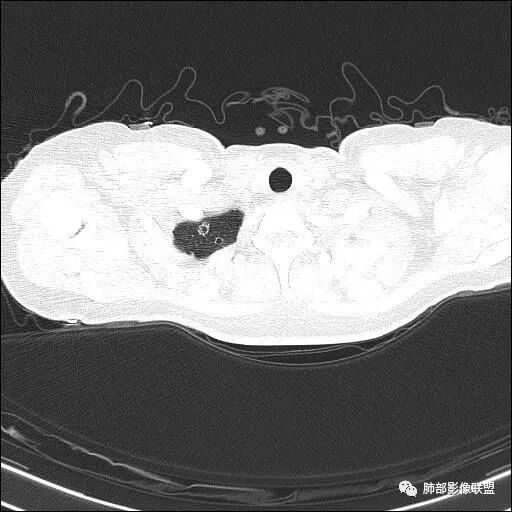

两肺多发病灶

分布特点:上肺胸膜下

图太少了,不连续,都是切面问一句:大家不觉得是沿间质分布的吗?网格状吗肿瘤不考虑吧如果单独拿这一个出来,要警惕肿瘤

全部拿出来,好像就不符合

局限,内部密度低

结核不支持,结核,如果空洞,内部干净,壁光滑这个不符合考虑肺气肿合并感染

觉得还是以网格为主,就是间质为主的特点

只是稍膨隆,密度稍低高密度灶符合网状为主,所以朝肺气肿考虑